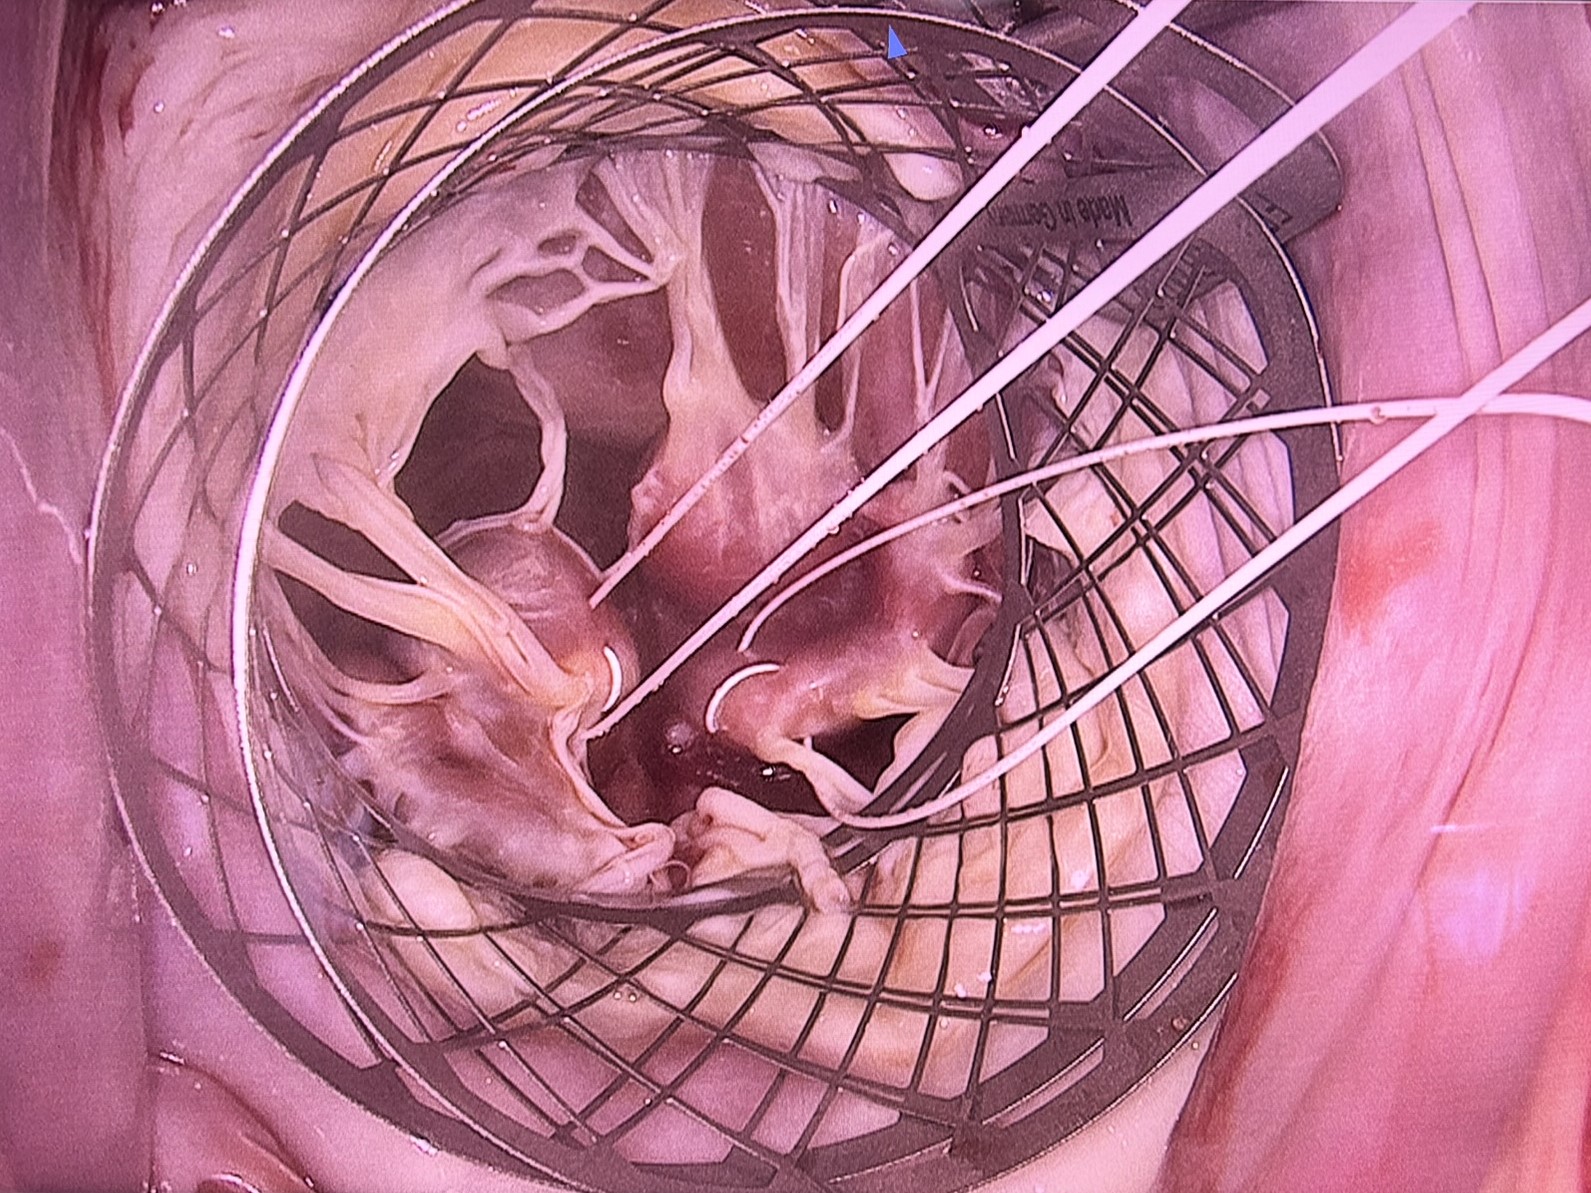

În functie de mecanismul regurgitarii mitrale, se aplica diferite metode de plastie ale acesteia:

Procedura comuna în reparatia valvei mitrale o reprezinta anuloplastia cu inel. Anuloplastia se realizează prin montarea unui inel sintetic cu rolul de a reda si a stabiliza forma corectă a inelului valvei mitrale a pacientului.